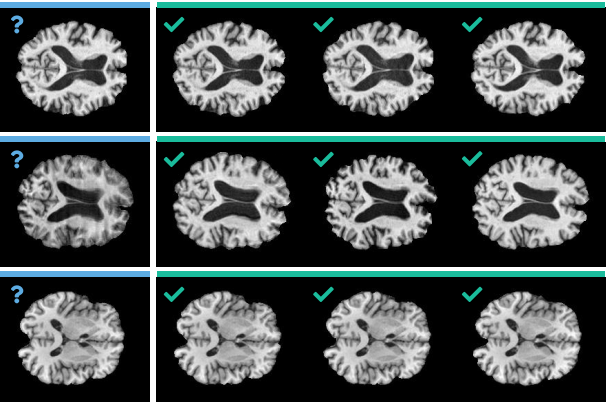

DeepBrainPrint è un framework di deep learning contrastivo per la ri-identificazione di soggetti tramite...